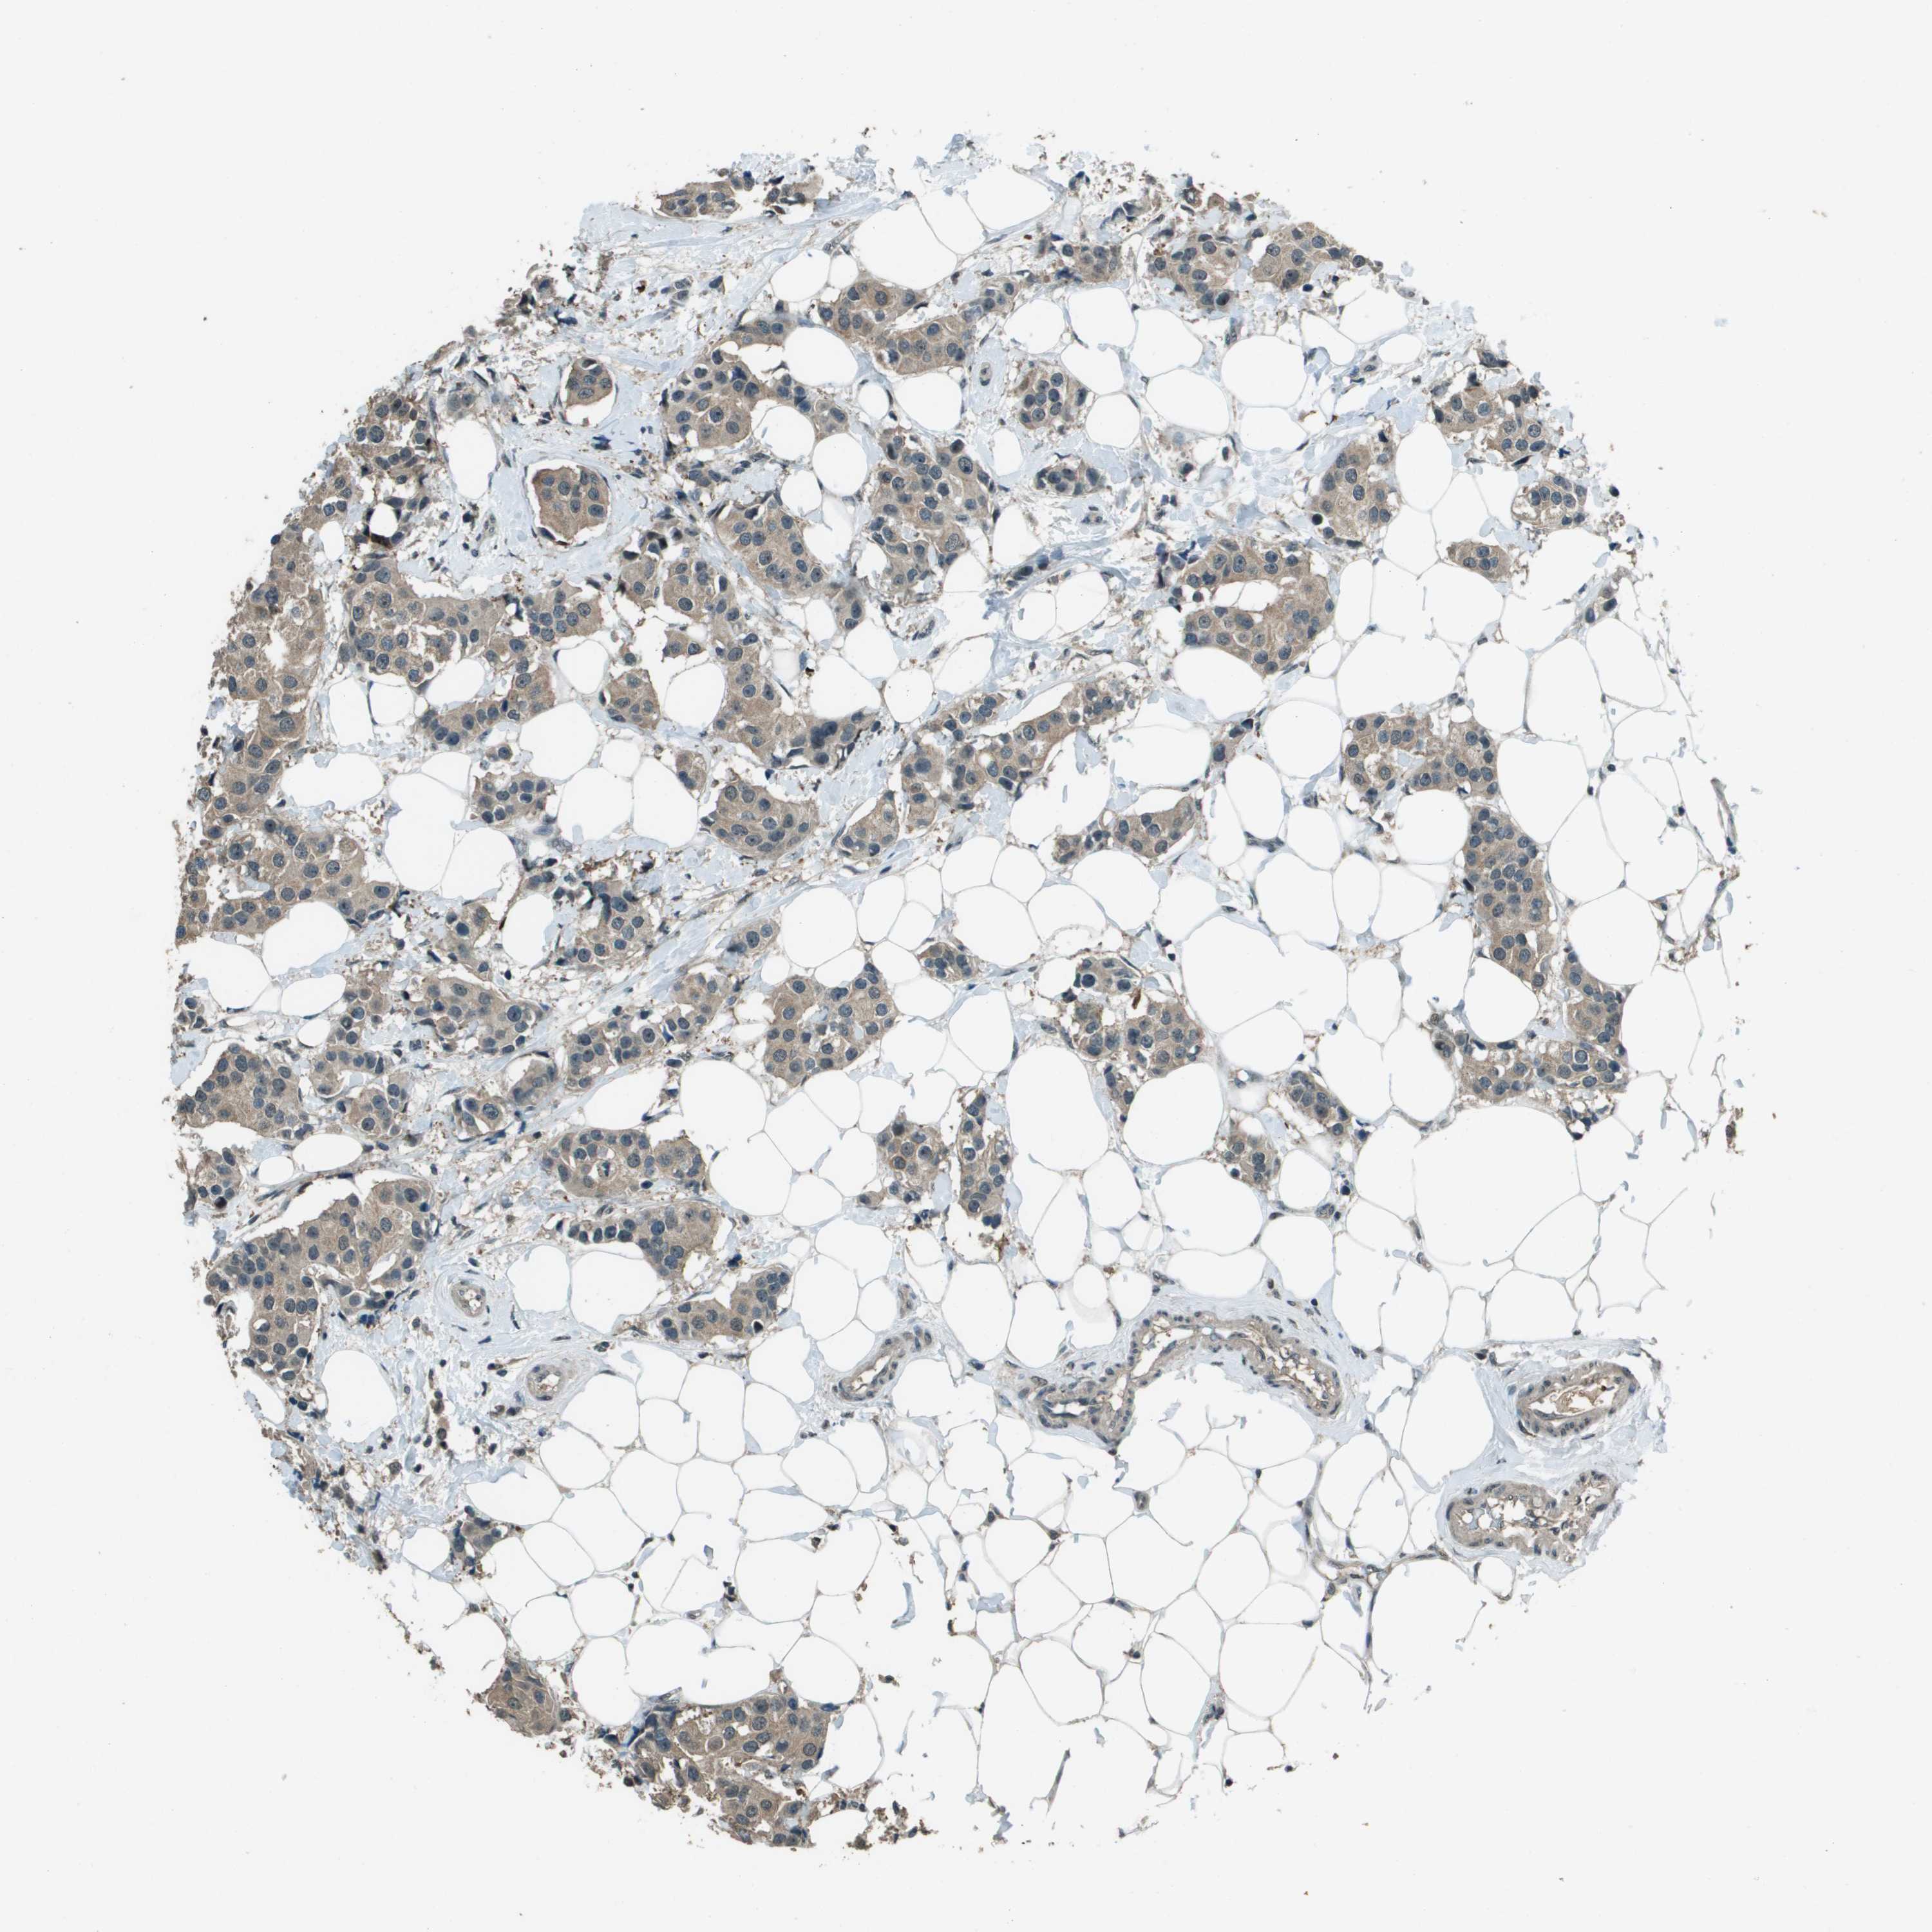

CANCER BREAST CANCER Show tissue menu

BRCA TCGA BRCA VALIDATION PROTEIN EXPRESSION

ANTIBODIES

AND

VALIDATION